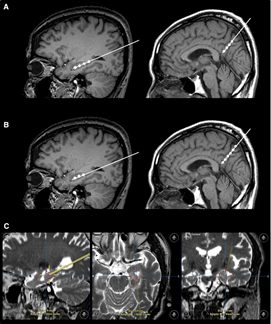

不僅如此,干細胞輸注治療安全可行。一項“立體定向腦內注射人間充質(zhì)干細胞治療AD病人”的臨床試驗結果表明,在治療結束后的24個(gè)月隨訪(fǎng)時(shí)間內,患者沒(méi)有出現與干細胞治療相關(guān)的嚴重的不良反應。

2023年1月24日,國際學(xué)術(shù)期刊Movement Disorders (運動(dòng)障礙)發(fā)表一篇研究性文章。研究者從胎兒中腦分離制備出多巴胺神經(jīng)祖細胞,移植到患者的大腦中。設計方案:給15名患者(年齡<70歲)注射了三種劑量的細胞量(4×10*6,12×10*6,40×10*6細胞),隨后進(jìn)行12個(gè)月的隨訪(fǎng)。研究結果顯示:低劑量組的運動(dòng)能力恢復效果為11.6%,中劑量組為26%,高劑量組為40%。此外,沒(méi)有副作用,如出血、免疫排斥、炎癥和腫瘤形成。